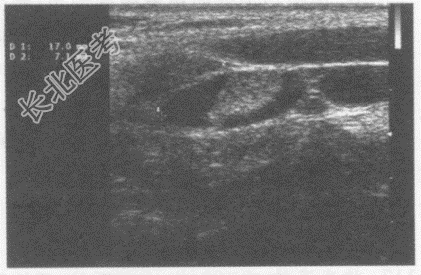

- 单项选择题男,25岁, 自述发热,嗓子痛。临床物理检查: 扁桃体红、肿大,体温39.0℃。超声综合描述: 双侧颈部血管旁可见数个两头稍尖长圆形低回声,最大1.7cm×0.7cm, 边界清晰,长径/短径比值(L/S)≥2。超声提示:

B、双侧颈部肿大淋巴结(颈淋巴结炎)